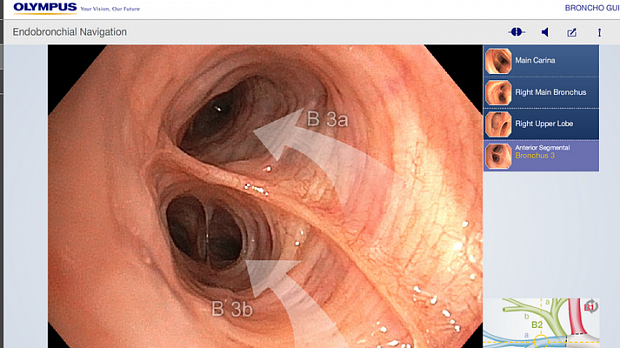

Вы выполняете, приближенное к реальности, обследование бронхиального дерева в HDTV качестве бронхоскопом BF-H190.

Реализована функция внутрипросветной эндонавигации по бронхиальному дереву!

Вы сможете последовательно начиная от карины, используя тачскрин, выбирать направление и изучать\вспоминать анатомию бронхиального дерев

Комментарии диктора статичных изображений и переходные видео применены для максимального облегчения пространственной ориентации и подробного объяснения о ангуляции и движении бронхоскопа во время исследования.ВИДЕО работы приложения можно посмотреть на сайте разработчика:

You are welcome to experience a bronchoscopic examination, almost as if it were done in a real clinical setting. Starting at the main carina, this app enables you to steer a HDTV bronchoscope through the bronchial tree step-by-step, from one carina to the next. Audio commentated still images and transitional videos are displayed facilitating spatial orientation and providing detailed explanation about the angulation and movement of the bronchoscope. Highly experienced medical experts have been involved in the development of this training app; however, please keep the following aspects in mind: